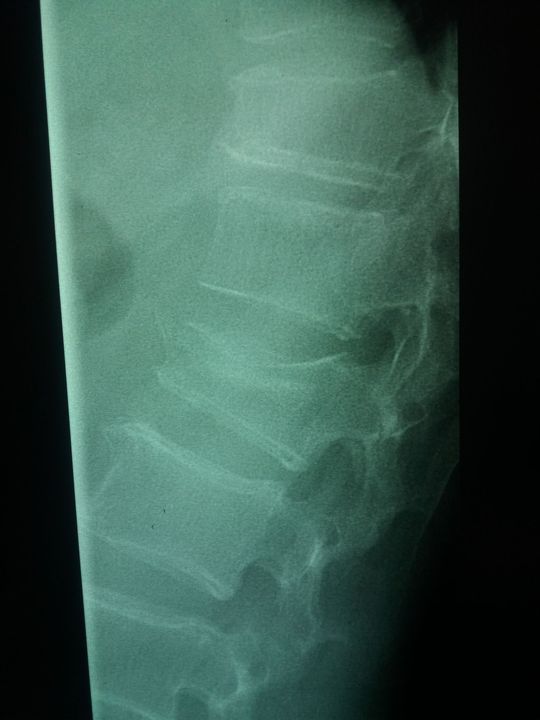

Find the problem

Xray

Vertebral

Looks like a compression fracture

Çökme kırığı var Murad